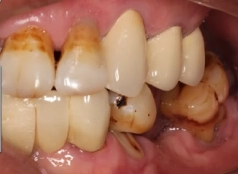

• Tình trạng răng trước đây:Mất nhiều răng ở cả 2 hàm, bị viêm nha chu nhiễm trùng

• Bác sĩ chỉ định:Nhổ các răng nhiễm trùng và cấy ghép 10 trụ Implant

Từng là người rất chủ quan về vấn đề vệ sinh răng miệng cộng thêm việc ăn uống nóng lạnh quá nhiều khiến cho chú Đình Hảo hư hỏng và mất nhiều răng. Dẫn tới sức khỏe và tâm lý của chú cũng bị ảnh hưởng.

Khi đến thăm khám tại nha khoa I-Dent, chú Hảo đã có những tâm sự về tình trạng răng trước đây của mình: “Chú từng rất chủ quan về vấn đề răng, không có để ý vệ sinh kỹ lưỡng, rồi ăn uống cũng hay ăn nóng sôi. Chú hỏng răng cũng vì ăn nóng nhiều quá. Đến khi mất răng rồi mới biết nhiều khó khăn, bất tiện lắm”.

Chú Hảo là người rất quan trọng những bữa cơm cùng gia đình, nhưng từ ngày mất răng chú hầu như không còn cảm giác ăn uống ngon miệng nữa. Thay vào đó là sự đau nhức, khó chịu, thỉnh thoảng còn sưng viêm làm chú thêm mệt mỏi.